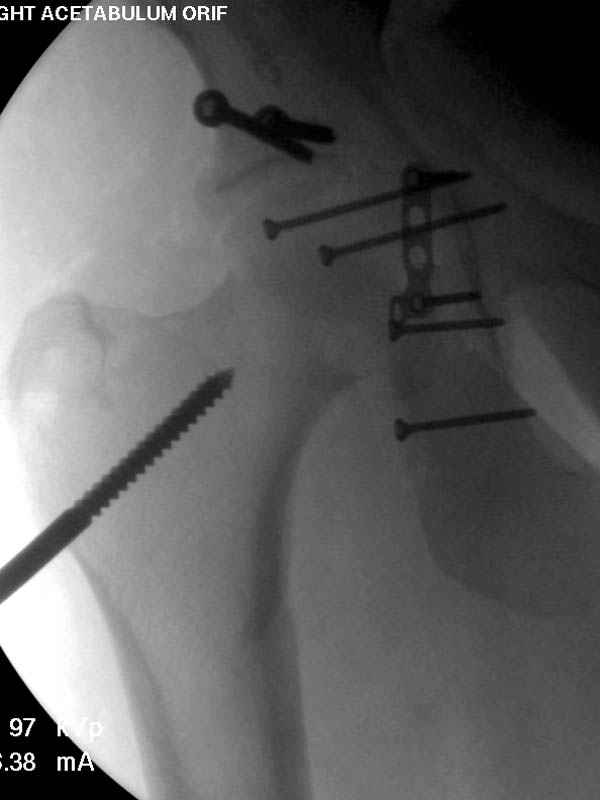

Дополнительно имеется перелом ацетабулума: задняя

колонна с полупоперечным переломом, и переломы костей лица.

На седьмой день зафиксирован перелом ацетабулума через задний доступ. Перед операцией для профилактики DVT, IVC фильтер, также получает Lovenox.

Извиняюсь за качества снимков, обычный больной в 300 фунтов, портативным ренген аппаратом не пробить.

Там множество обычных 2.7 мм шурупов, потом идет фиксация основными пластинами.

Снимки здесь....